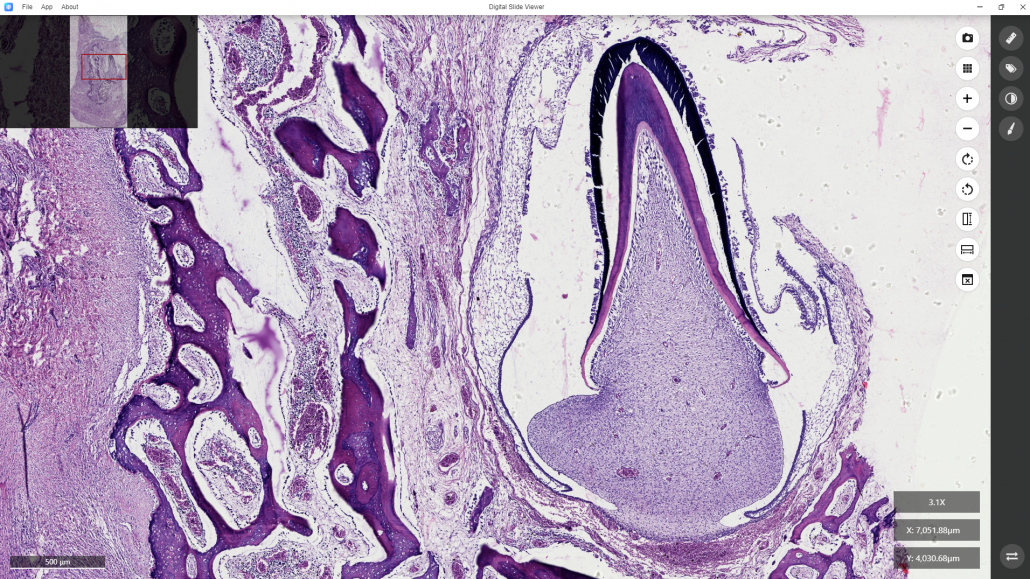

Here, for example, you want to observe the detailed structure of a developing tooth.

You may lock on the target and continue to enlarge the image by turning the mouse scroll wheel forward or clicking the “+” command at the right bar of the software, the image can be enlarged.

In contrast, turning the mouse scroll wheel backward or clicking the “-” command at the right bar of the software will shrink the image. Then the enlarged image is shown.